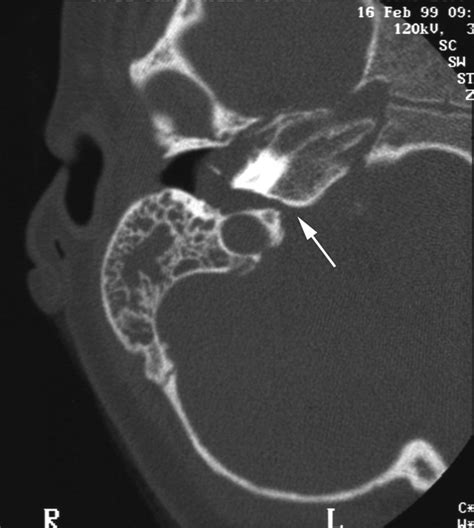

• Imaging Tests: Imaging tests, such as CT scans or MRIs, may be ordered to assess the structures within the ear and surrounding areas.